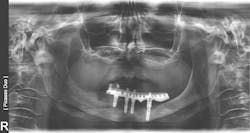

In addition to patient-related factors, a site-specific negative effect on bone healing has also been suggested. Sites of previous implant or graft failure will have compromised alveolar bone quality and quantity compared with unoperated sites. Thus, significantly lower survival rates of implants placed in sites of previous failure have been reported compared to initial implants, supporting evidence of site factors for failures.5 This site-specific theory is further supported by the finding that failed implants are often found in patients who have also had successful implants placed at other sites (figures 5a–5c).

Figures 5a–5c: Successive implant failures and bone augmentation in the right posterior mandible, resulting in compromised bone healing and subsequent chronic osteomyelitis.